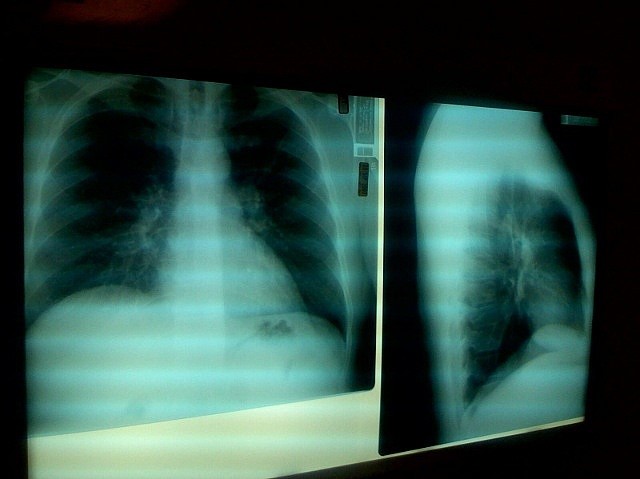

VALÈNCIA. (EP). El consumo de analgésicos opiáceos aumenta un 30 por ciento el riesgo de neumonía en personas con enfermedad de Alzheimer, según muestra un estudio reciente de la Universidad de Finlandia Oriental. Según sus hallazgos, publicados en la revista 'Journal of Alzheimer's Disease', este riesgo fue más pronunciado en los dos primeros meses de uso.

La incidencia de la neumonía fue mayor entre los que utilizaban opiáceos fuertes, como oxicodona o fentanilo, pero también se incrementó entre los que utilizaban buprenorfina, tramadol o codeína. Las personas con cáncer fueron excluidas del estudio, y otras enfermedades y el uso de drogas se tuvieron en cuenta en los análisis. Los investigadores puntualizan que los opiáceos perjudican la tos y las funciones respiratorias y causan sedación, lo que posiblemente subyace al mayor riesgo de neumonía.

La neumonía es una complicación grave pero relativamente frecuente entre las personas con enfermedad de Alzheimer, y a menudo conduce a la hospitalización e incluso a la muerte. Los opiáceos son importantes en el tratamiento del dolor agudo severo, pero el tratamiento debe iniciarse en dosis bajas y evaluarse regularmente tanto en términos de beneficios como de daños.